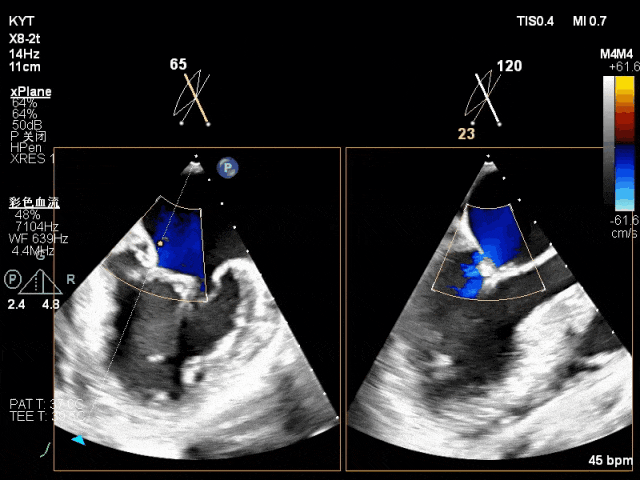

术前超声评估结果:

二尖瓣PC区收缩期脱向左房侧,其上可见飘带样回声。二尖瓣口左房侧见大量反流信号,主要呈偏心性并沿前叶走行达房顶并折返。

TEE X-plane示二尖瓣内交界区脱垂

TEE X-plane with color Doppler